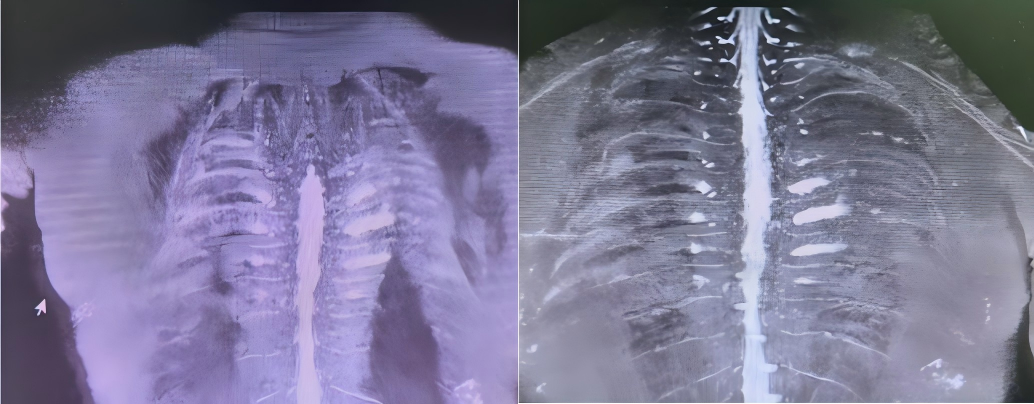

胸部CT:1、双肺间质纹理增多;2、肝右叶点状钙化灶。

图1. 胸椎磁共振:左侧胸3-5神经相对侧显示浅淡,胸1-5左侧侧索T2信号增高